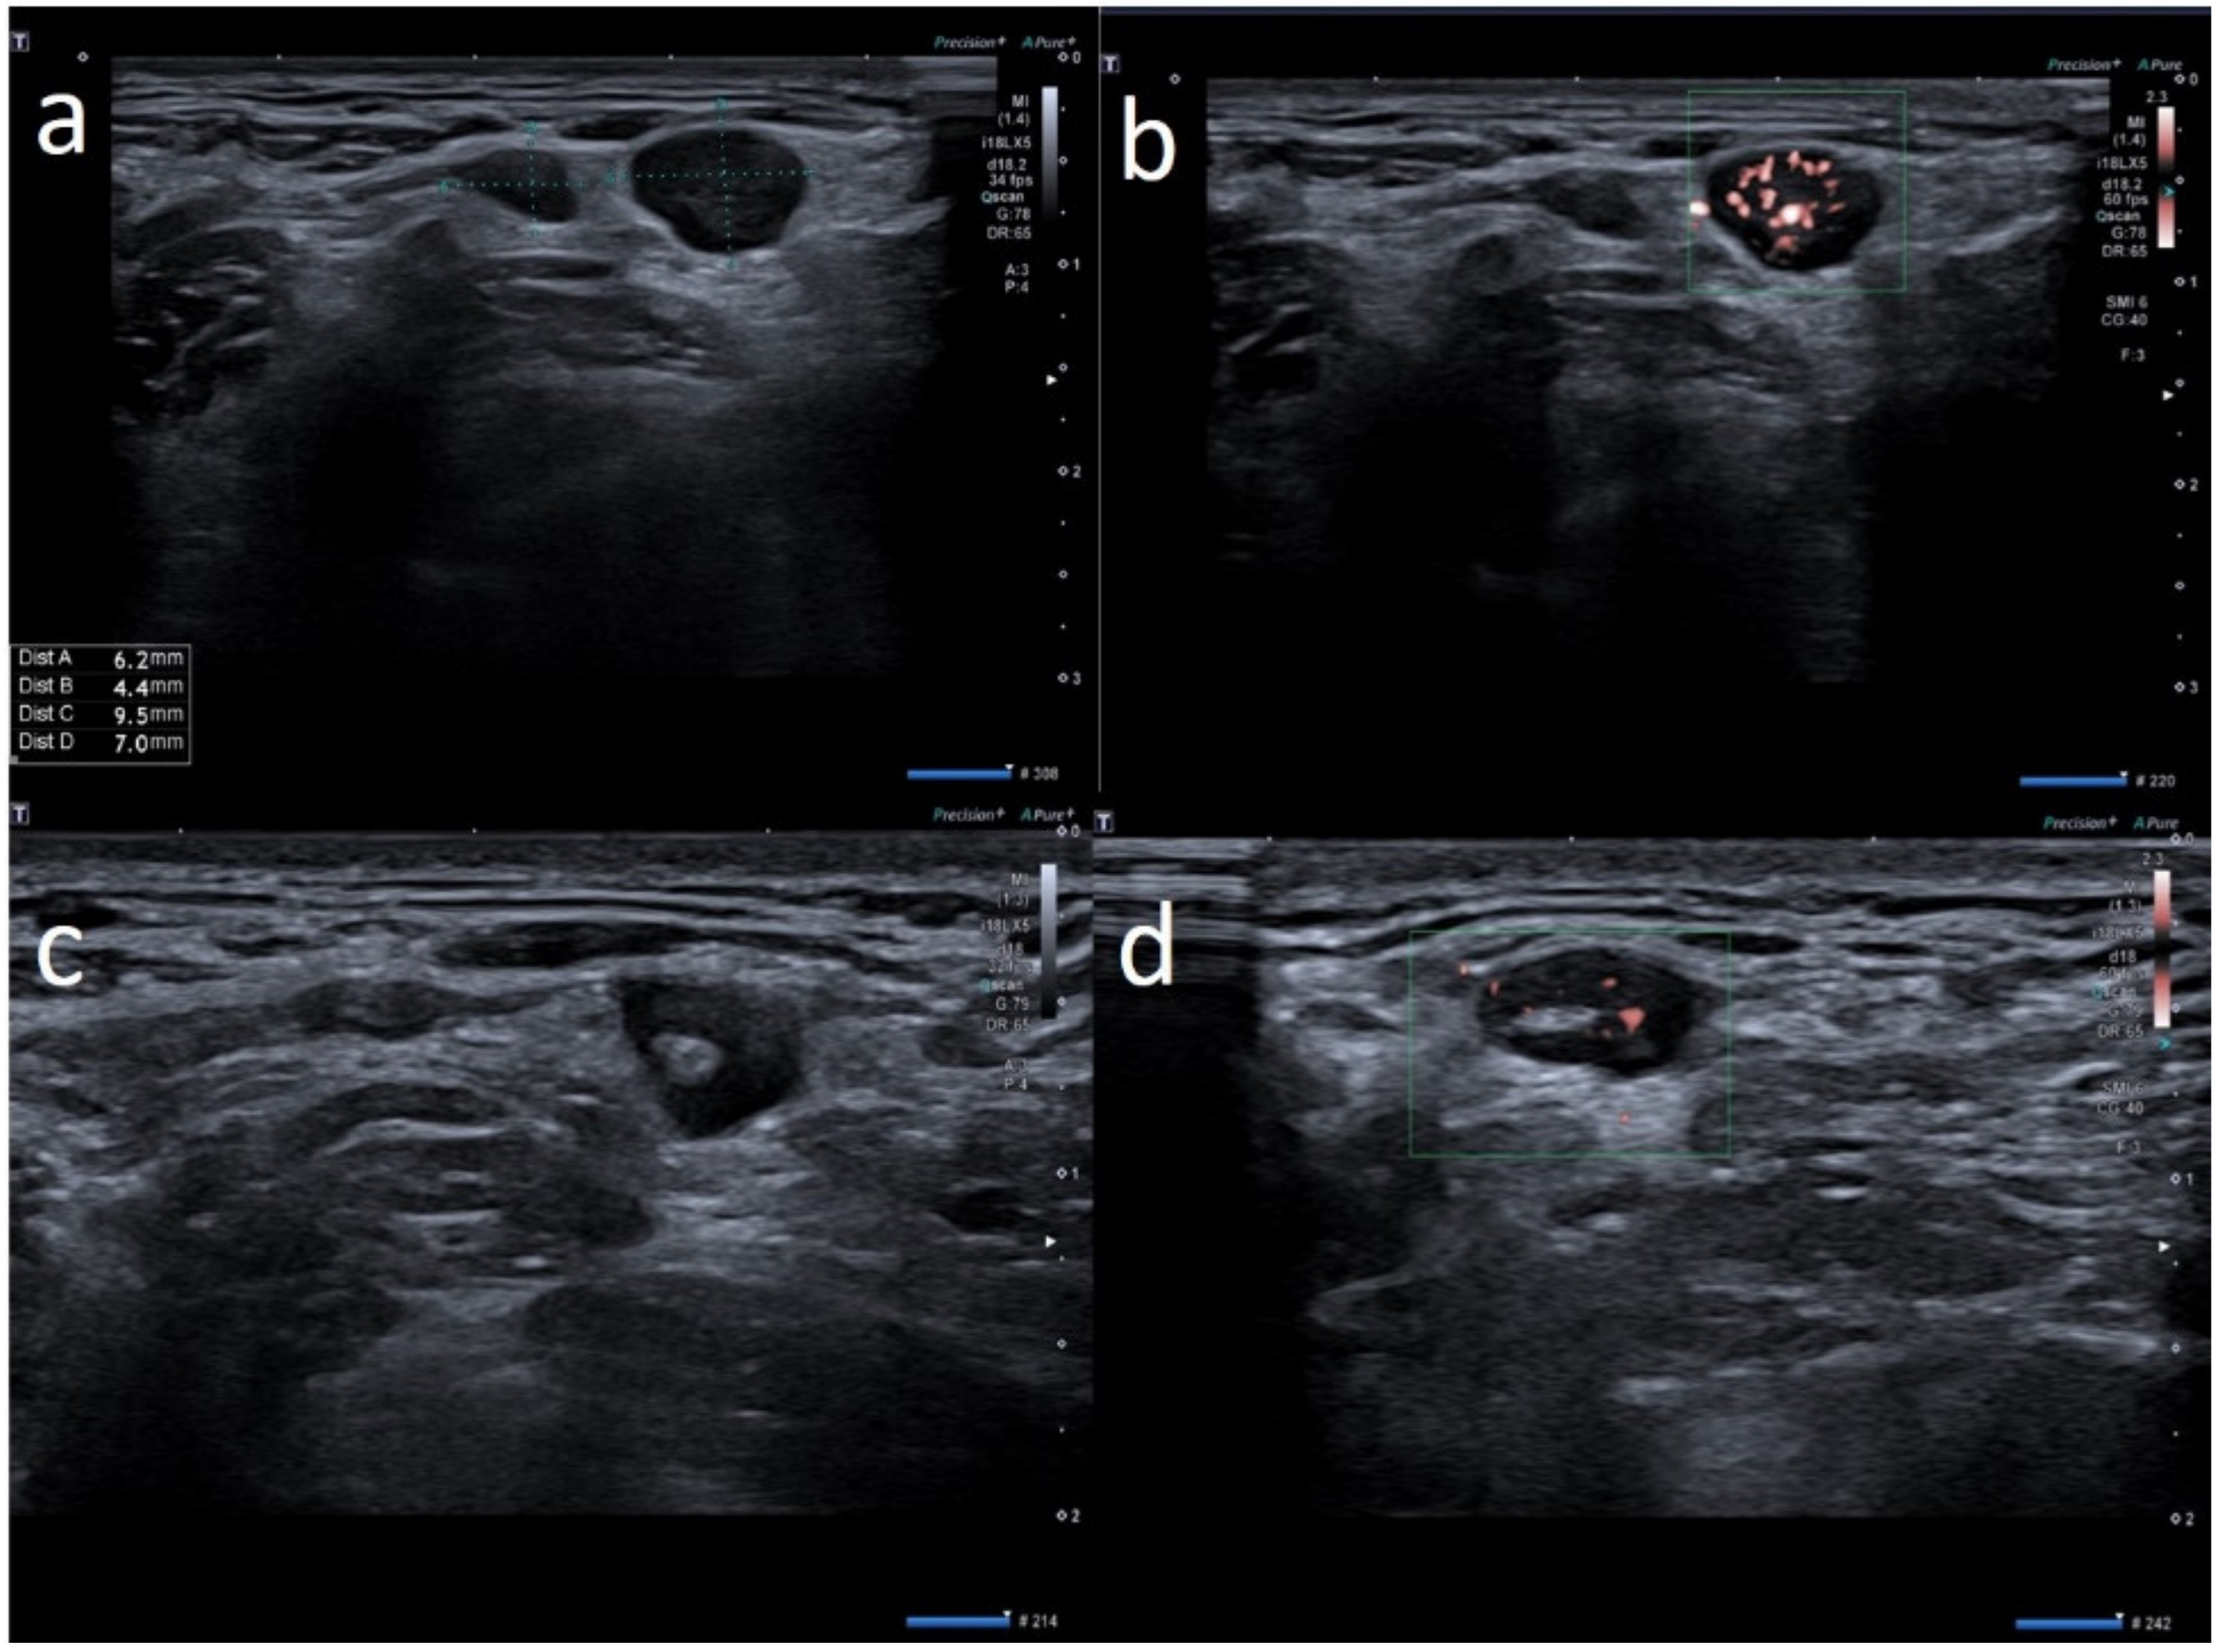

| W | 25 | Pfizer | Axillary ipsilateral to vaccine injection | Three days after first dose of vaccine, axillary swelling and pain present. Also hypomobility ipsilateral arm | None | 6 | Variable: from 0.7 cm to 2.8 cm | Ovular | Prev. no hilum evidence | Prevalent hard pattern | Central and peripheral vascular signals | Normalized to 60 days |

| W | 28 | Astazeneca | Supraclavicular ipsilateral to vaccine injection | Two days after first dose vaccine, supraclavicular swelling and pain present | None | 3 | Variable: from 0.6 to 1.5 cm | Ovular | No evidence hilum | Prevalent hard pattern | Central and peripheral vascular signals | Normalized to 45 days |

| W | 72 | Astazeneca | Supraclavicular ipsilateral to vaccine injection | One day after first dose vaccine, supraclavicular swelling and pain present | None | 2 | Subcentimetric size | Round | Asimmetric cortical thickening with hilum evidence | Prevalent hard pattern | Peripheral vascular signals | Normalized to 30 days |

| M | 39 | Astazeneca | Supraclavicular ipsilateral to vaccine injection | Four days after first dose vaccine, supraclavicular swelling and pain present | None | 1 | Subcentimetric size | Round | No evidence hilum | Prevalent hard pattern | Central and peripheral vascular signals | Normalized to 30 days |

| M | 41 | Moderna | Supraclavicular ipsilateral to vaccine injection | Two days after first dose vaccine, supraclavicular swelling and pain present | None | 3 | Subcentimetric size | Ovular | No evidence hilum | Stiffness similar to surrounding tissue | Central and peripheral vascular signals | Normalized to 30 days |

| M | 35 | Pfizer | Supraclavicular ipsilateral to vaccine injection | Day after the first dose vaccine, supraclavicular swelling and pain present | None | 1 | Around 1.5 cm | Round | No evidence hilum | Prevalent hard pattern | Central and peripheral vascular signals | Normalized to 60 days |

| W | 26 | Astazeneca | Supraclavicular ipsilateral to vaccine injection | 2 days after the first dose vaccine, axillary swelling and pain present | None | 5 | Subcentimetric size | Ovular | No hilum evidence | Prevalent hard pattern | Central and peripheral vascular signals | Normalized to 45 days |

| F | 32 | Astrazeneca | Supraclavicular ipsilateral to vaccine injection | Day after first dose vaccine, supraclavicular swelling and pain present | None | 1 | Around 1.2 cm | Round | No evidence hilum | Prevalent hard pattern | Central and peripheral vascular signals | Normalized to 30 days |

| F | 29 | Pfizer | Supraclavicular ipsilateral to vaccine injection | Day after first dose vaccine, supraclavicular swelling and pain present | None | 2 | Subcentimetric | Round | No evidence hilum | Prevalent hard pattern | Central and peripheral vascular signals | Normalized to 30 days |